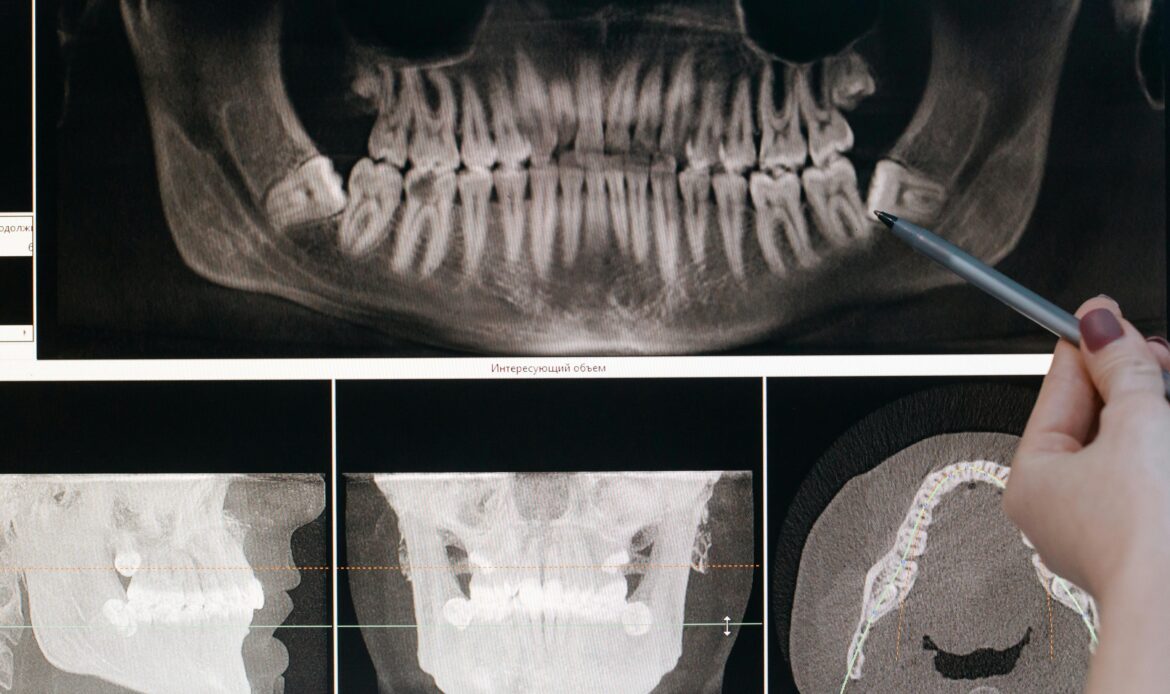

Evaluación y manejo de trastornos temporomandibulares (ATM)

-Valoración clínica de dolor mandibular, chasquidos, limitación de apertura y tensión muscular. -Orientación y tratamiento para mejorar la función de la articulación temporomandibular.